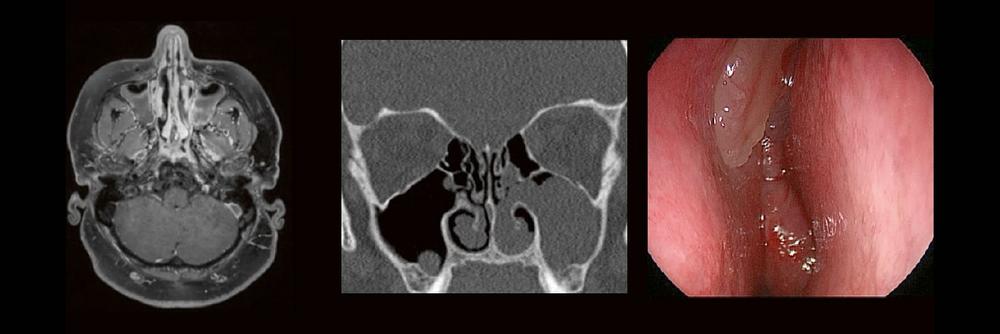

Die bildgebende HNO-Diagnostik macht es Anfängern nicht leicht. Die Anatomie ist komplex und weniger intuitiv als in anderen Körperregionen.

Normvarianten erschweren insbesondere in den Nasennebenhöhlen den Lernprozess. Sobald pathophysiologische Zusammenhänge verstanden und wichtige klinische Aspekte verinnerlicht wurden, gelingt es einen praxistauglichen, belastbaren Befund zu erstellen.

Begleiten Sie uns auf einer kooperativen Reise durch die NNH mit „Ach so!“-Garantie:

Gemeinsam mit einem HNO-Chirurgen werfen wir einen Blick IN die NNH – mal in grau, mal in Farbe. Denn alles fällt leichter, sobald man verstanden hat, warum man es tut.